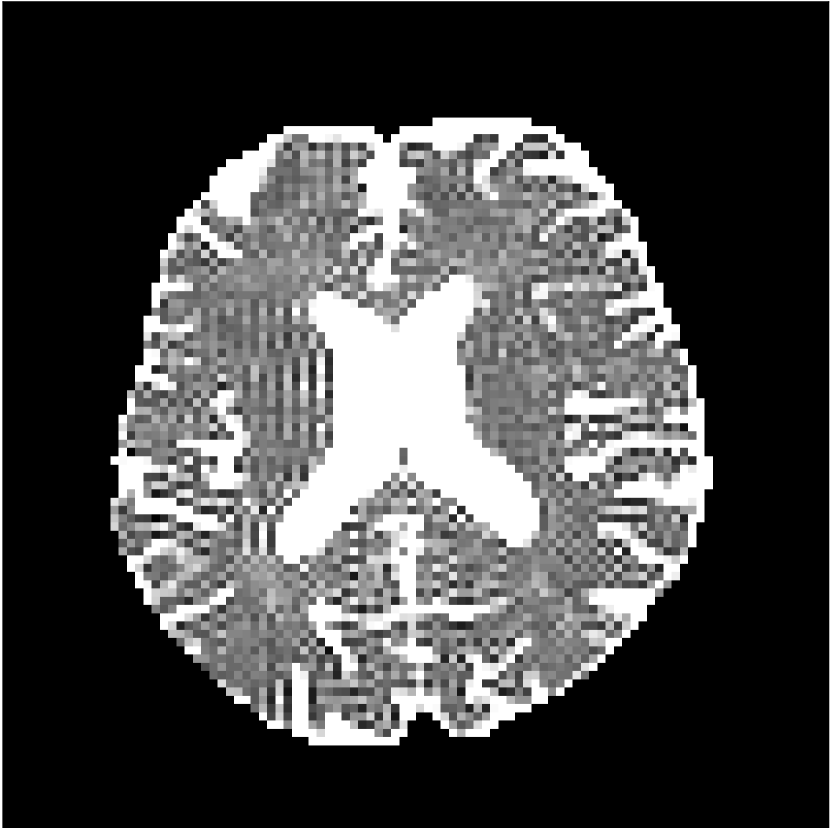

Figure 10 compares mean diffusivity maps across various partial Fourier factors between the CCNN and state-of-the-art methods.

No PF

7/8 PF

6/8 PF

5/8 PF

SoA

MD, m2/ms

CCNN

The methods perform similarly without partial Fourier acceleration, but as partial Fourier acceleration increases, the image is continually degraded in the SoA method, with "black voxels" appearing around the lateral ventricles. The CCNN method mitigates the appearance of these artifacts in the parameter maps.